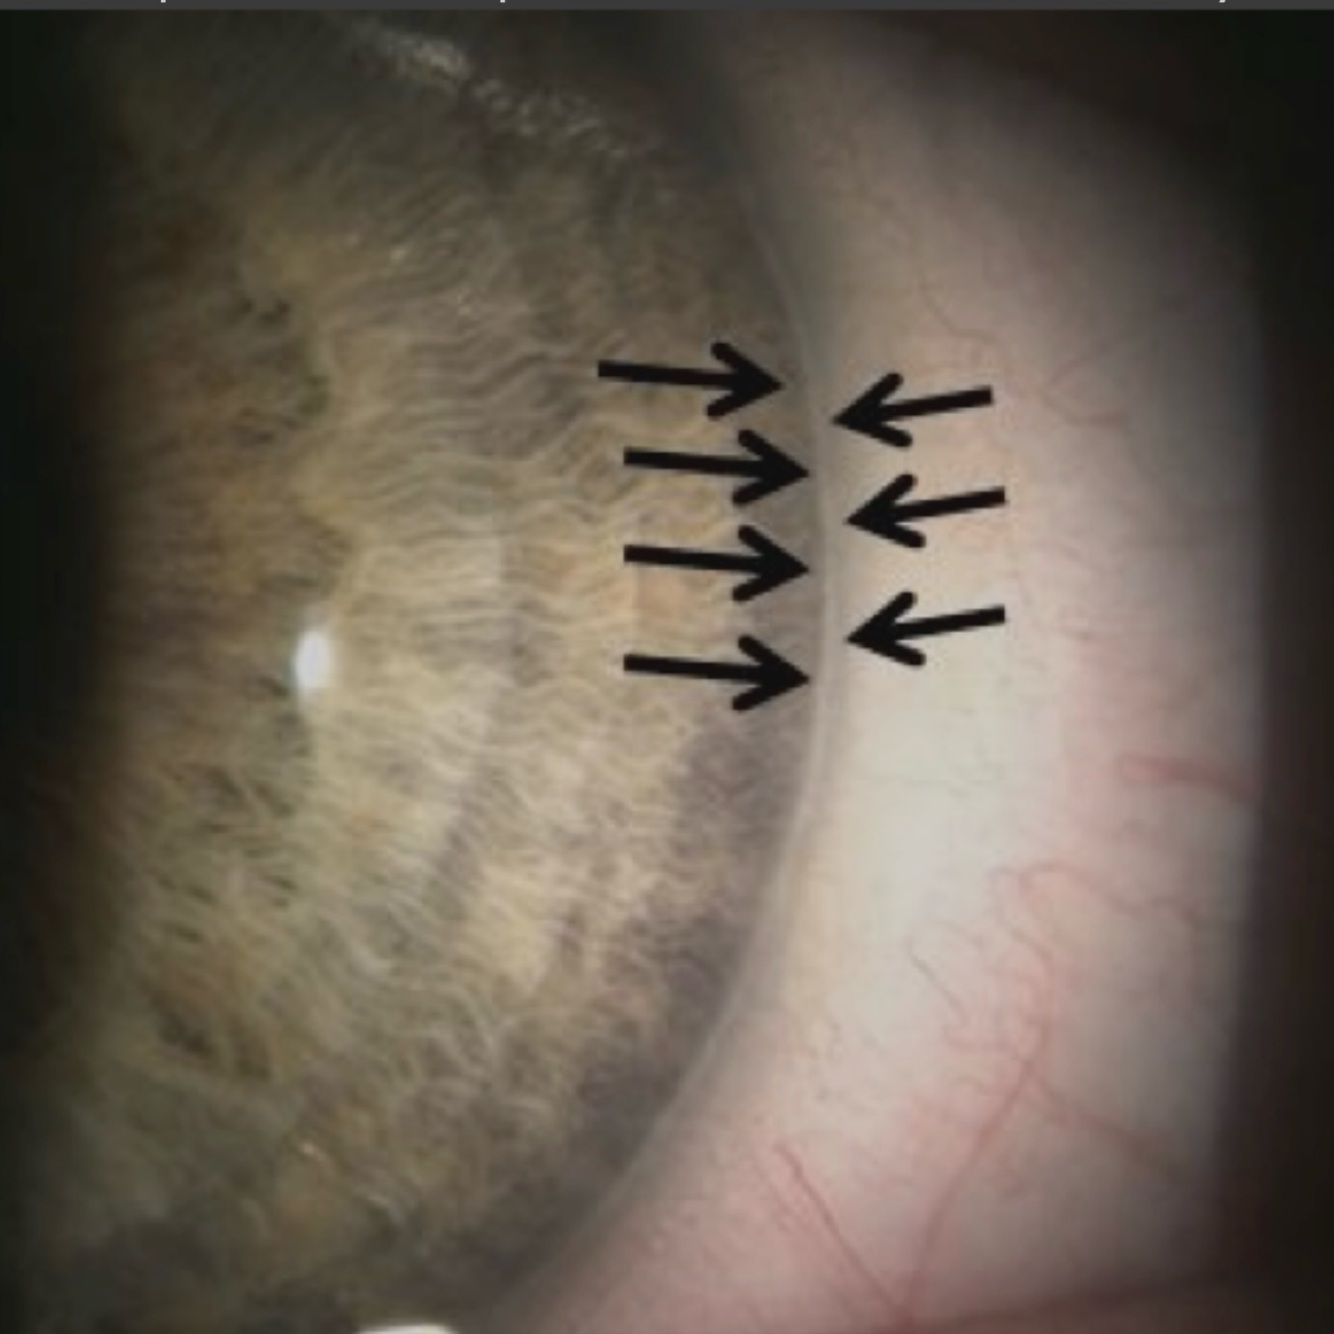

Posterior embryotoxon

*anteriorly displaced Schwalbe line

* no treatment at this time

* RTC: annual for CEE